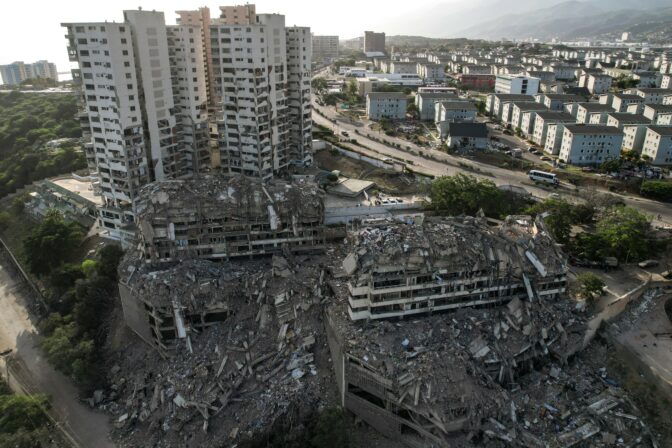

Implantované časti umelého srdca Zdroj: NÚSCH

Implantované časti umelého srdca Zdroj: NÚSCH